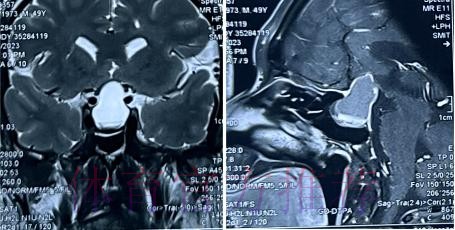

在高速对抗的现代足球里 现场肉眼和赛后情绪往往会放大对伤情的判断 一名球员倒地呻吟或无法坚持比赛 很容易被解读为韧带断裂 或肌肉严重撕裂 但真正决定恢复周期的关键因素 通常要到核磁共振检查之后才会明朗 因为核磁能在较早阶段清晰显示软组织 肌肉 韧带以及骨结构的微小损伤情况 对伤情做出更接近真相的分级判断 塞巴略斯此次就是典型案例 初步观感可能让人联想到更严重的伤病 但核磁提示伤情相对可控 没有出现完全断裂或大面积撕裂 也就意味着他不需要漫长的康复旅程 只要遵循医学建议 科学负荷管理 就有机会用较短的时间重新回到训练场和比赛中

塞巴略斯这一类型的技术中场 通常触球频繁 变向急促 需要大范围穿插跑动 在这种比赛习惯下 肌肉和韧带承受的累积负荷极高 尤其在密集赛程和高压对抗中 任何一次小小的失衡或强硬对抗 都可能放大为潜在伤病 因此外界对他伤情格外敏感 并非夸张反应 而是基于过往大量案例得出的经验判断 从厄德高 德布劳内 再到其他同类型中场 很多球员都在职业生涯某个阶段与伤病长期共存 一旦错过最佳治疗和恢复窗口 轻伤有可能拖成旧患 进而影响球员的爆发力 节奏控制能力乃至职业寿命 在这一背景下 经核磁共振检查确认 塞巴略斯伤情没有预期严重 其实反映的是球队在医疗体系 与负荷管理上的相对成熟 至少在第一时间 做到了科学评估 而不是情绪化处理

经核磁共振检查确认 塞巴略斯伤情没有预期严重 这一结果从某种意义上是一种系统胜利 首先是医疗系统的胜利 医疗团队在第一时间介入 选择最合适的影像学手段 明确伤情边界 避免了盲目乐观或过度保守 其次是管理系统的胜利 俱乐部没有急于利用球员的意愿 扮演所谓硬汉形象 而是尊重科学节奏 为他预留足够的恢复空间 再次是沟通系统的胜利 球员 经纪人 医疗小组和教练组之间保持信息畅通 能够在保护球员未来和保证球队眼前成绩之间找到平衡点 正是这些系统共同作用 才让一次看似危机四伏的受伤 逐步转化为可控 可恢复的阶段性波折